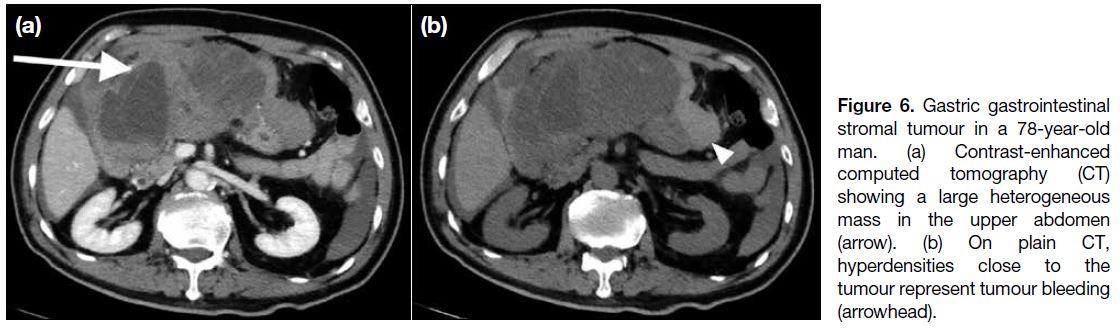

may extend into the gastrohepatic ligament, gastrosplenic ligament or lesser sac (Figure 5a). Endoscopic ultrasonography is useful to identify the layer of origin of the mass (Figures 4b, 5b and 5c). Gastric GISTs may also be complicated by perforation or bleeding

(Figure 6).

Figure 6. Gastric gastrointestinal stromal tumour in a 78-year-old man. (a) Contrast-enhanced computed tomography (CT) showing a large heterogeneous mass in the upper abdomen (arrow). (b) On plain CT, hyperdensities close to the tumour represent tumour bleeding (arrowhead).